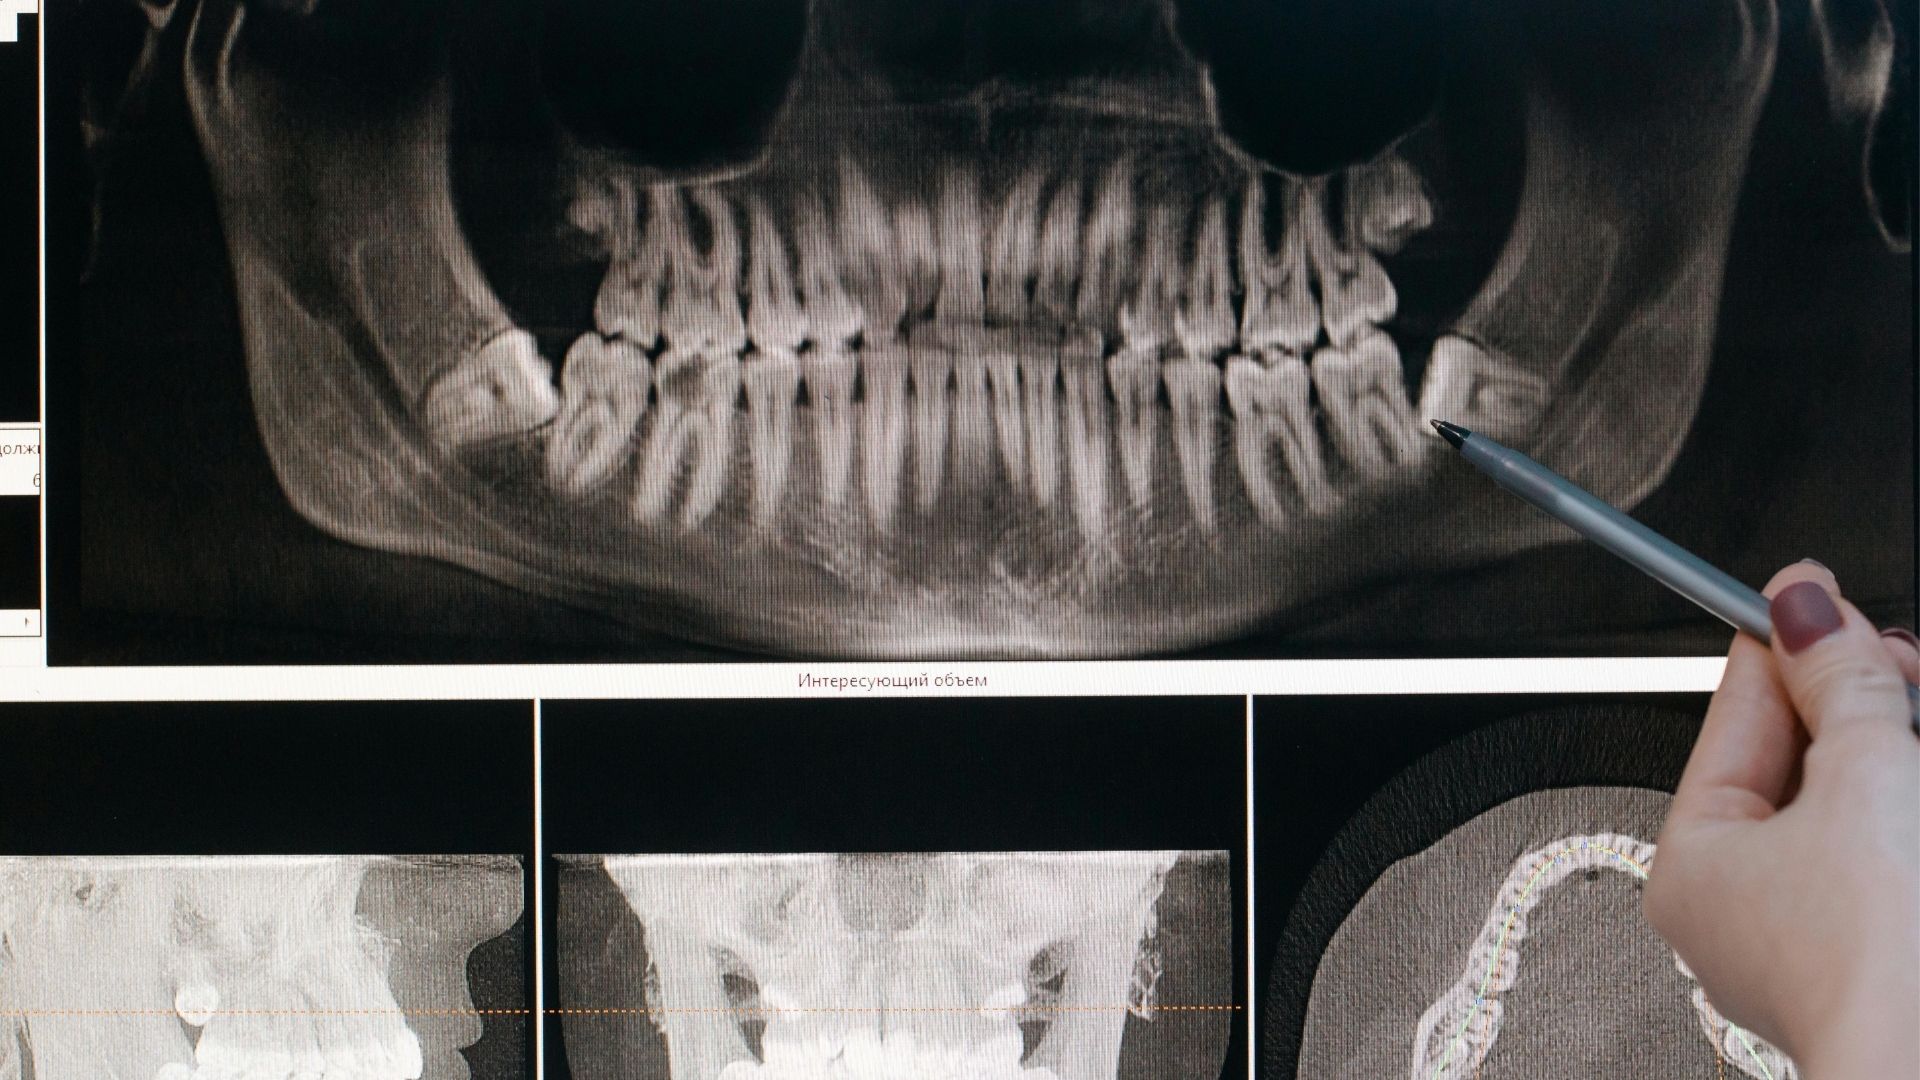

A bölcsességfog eltávolítása akkor válik aktuálissá, amikor a fog teljesen kifejlődött, ám sok esetben az előtörés meg sem történik. Az első lépés mindig egy panoráma röntgenfelvétel készítése, amely megmutatja a bölcsességfogak pontos helyzetét és fejlettségi állapotát. Egyszerű foghúzásra akkor kerül sor, amikor a fog legalább 90%-ban előtört, míg bölcsességfog műtétről akkor beszélünk, amikor csak kis mértékben vagy egyáltalán nem látszik, hanem a csontban fekszik. A korai diagnózis és kezelés segít elkerülni a későbbi, súlyosabb komplikációkat és fájdalmakat.

A bölcsességfog műtét első lépéseként panoráma röntgenfelvétel készül, amely alapján a fogorvos felméri a beavatkozás pontos menetét. Bonyolultabb esetekben CBCT-vizsgálatra is szükség lehet, különösen az alsó bölcsességfogak esetében, ahol fontos tisztázni az ideg pontos elhelyezkedését a gyökerekhez képest. A beavatkozás helyi érzéstelenítésben történik, amely során az íny felvágásával feltárják a fogat, szükség esetén kettévágják, majd a csont részleges eltávolításával kiemelik.